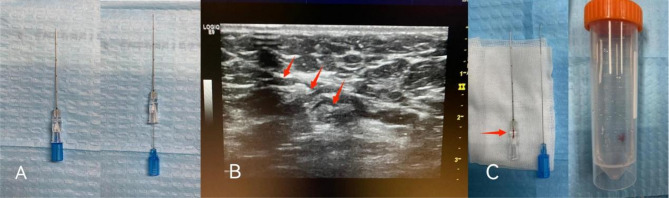

Methods: We compared the feasibility and diagnostic efficiency of using a novel procedure to FNA for the assessment of clinically positive nodes in patients with early breast cancer. Between 1 January 2015 and 30 September 2023, 198 consecutive patients who consented to undergo axillary biopsy were referred to either the intraoperative ultrasound-guided wire localization group (IOUS-wire) or the ultrasound-guided fine needle aspiration group (US-FNAC). The primary endpoint was the false-negative rate (FNR) and accuracy rates of the two methods. One hundred patients were in the IOUS-wire group, whereas the other 98 patients were in the US-FNAC group.

Results: The FNR of clinically positive lymph node biopsies was lower in the IOUS-wire localization group than in the US-FNAC group (16.1% versus 87.5%, p < 0.001). Among the 32 successfully identified metastatic lymph nodes, 26 (81.3%) were detected in the IOUS-wire group. In the US-FNAC group, 42 additional lymph node metastases were identified via SLNB among patients initially classified as FNAC-negative. The accuracy rates for IOUS-wire and US-FNAC were 95% and 57.1%, respectively (p < 0.001). No significant differences were observed in complications or median SLNs harvested between groups.

Conclusion: IOUS-wire localization with frozen sections demonstrated superior diagnostic performance compared to preoperative US-FNAC in patients with clinically node-positive early breast cancer. This novel method should be further pursued as a potential biopsy method for evaluating axillary node status, particularly in settings where rapid intraoperative decision-making is prioritized.